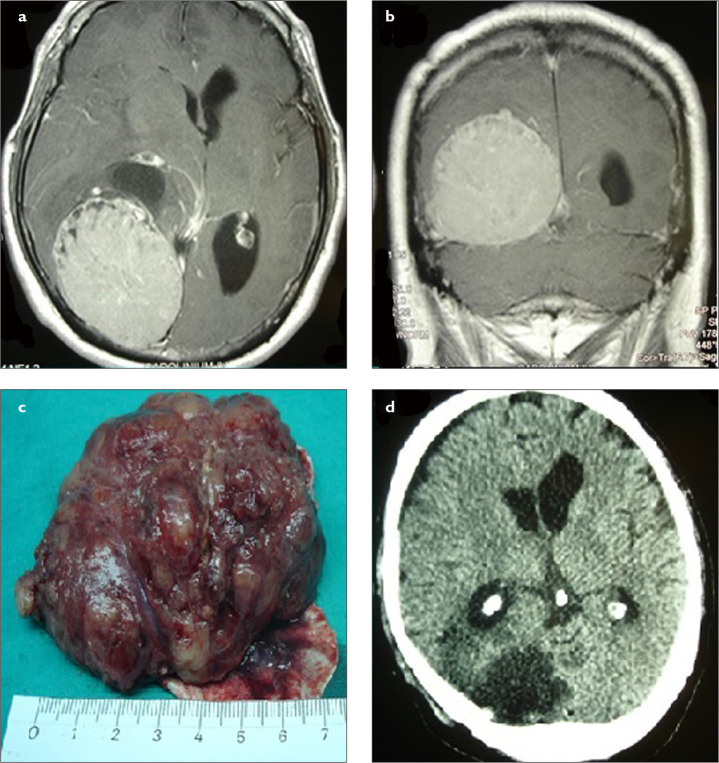

Objective: Giant intracranial meningiomas are a challenge for neurosurgeons because of their size and location in the cranium. Difficult tumor dissection and encasement of important neurovascular structures make them a horrible nightmare. The aims of this study are to present our giant intracranial meningioma series and to compare our experience using advanced surgical technology with the current literature.

Materials and methods: The data of patients with the diagnosis of giant intracranial meningioma between 2014 and 2020 who underwent surgical treatment were retrospectively reviewed. The demographic, radiological, and surgical characteristics of patients were documented. The size and location of tumors as well as surgical technique were analyzed in detail.

Results: A total of 61 patients with intracranial meningioma underwent surgical treatment over a 7-year period, and 10 (16.4%) tumors were larger than 5 cm in diameter, which were classified as giant meningioma. Seven patients were male and 3 were female, with a mean age of 64.9 years. Four tumors were located at the skull base. Histological diagnosis was meningioma World Health Organization grade I in 7 patients and grade II in 3 patients. Simpson grade 1 resection was achieved in 6 patients and grade 2 resection in 4 patients. No mortality was observed.

Conclusion: Careful surgical planning should be made for giant intracranial meningiomas. Their location, adjacent neurovascular structures, and vascular supply affect the resection level of these giant tumors. Simpson grade 1 resection is seldom possible for skull base meningiomas.